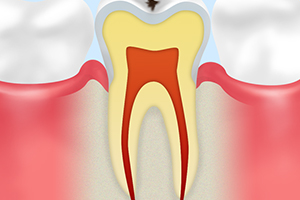

C0 脱灰

|

虫歯菌が出す酸によって、歯の表面にあるエナメル質が溶け始めた状態です。歯が白く濁って見えますが、痛みがないため注意して見なければ気づきません。 | この段階であれば、適切な処置によって治癒することもあります。歯科医院での定期検診やフッ素塗布で再石灰化を促しましょう。 |

C1 エナメル質の虫歯

|

虫歯菌によって歯の表面にあるエナメル質が溶かされた状態です。歯が黒ずんできますが、まだ痛みはないため気づく方はほとんどいません。 | 虫歯に侵された部分を削る必要があります。削った部分は簡単な詰め物をすることで修復します。 |

C2 象牙質の虫歯

|

虫歯菌がエナメル質の奥にある「象牙質」まで進行した状態で、普段は気にならないものの、冷たい物や甘い物を口にすると歯がしみるようになります。 | 治療の際には歯を削り、詰め物や被せ物で補います。大きく削った場合は詰め物では対応できないため、被せ物を使用します。 |